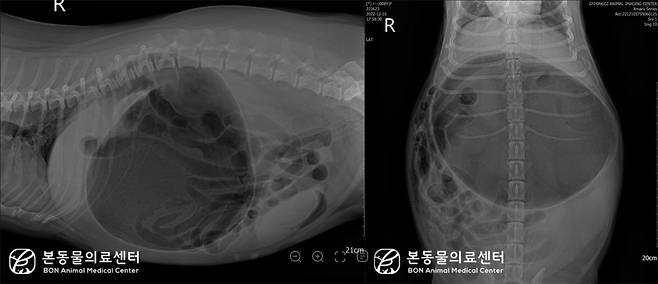

이은지 본동물의료센터 영상의학과장은 "혈액 검사 및 복부 방사선 사진을 찍자 위의 심한 확장과 위 유문부(십이지장으로 가는 통로 부위)의 등 쪽 전방 변위로 인한 위 내강이 분획화 된 소견이 확인됐다"며 "위염전으로 진단해 빠르게 수술에 들어갔다"고 설명했다.

웰시코기 종 반려견은 빠르게 위 고정술에 들어갔다. 수술 시 위가 시계방향으로 180도 회전되고 심하게 확장된 것이 확인됐다.